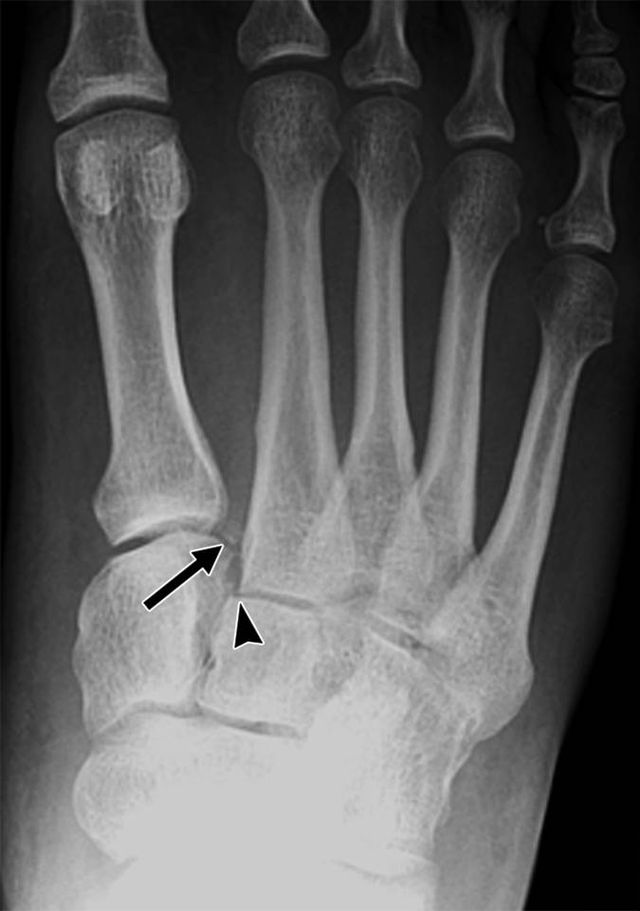

第五跖骨基底部裂纹骨折忧伤记录

这个属于骨裂还是骨折,不打石膏可以吗